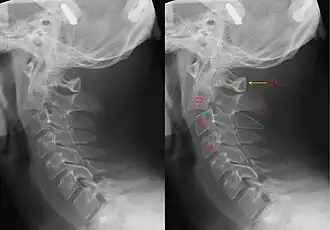

Hangman's fracture is the colloquial name given to a fracture of both pedicles, or partes interarticulares, of the axis vertebra (C2).[1]